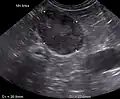

Zur Unterscheidung zwischen primärem und sekundären Hyperadrenokortizismus wird mittlerweile häufig auf die Ultraschalluntersuchung (Sonografie) der Nebenniere zurückgegriffen. Diese Untersuchungstechnik ist in der Tiermedizin mittlerweile breit verfügbar und kann Nebennierentumoren relativ sicher nachweisen. Generell ist die Nebenniere auch bei primären Cushing-Patienten vergrößert, da die gesteigerte Hormonproduktion zu einer Vergrößerung des Organs führt. Ein Querdurchmesser über 6 mm ist verdächtig für einen Hyperadrenokortizismus, die Sensitivität beträgt 75 %, die Spezifität 94 %.[24] Zudem lässt sich mittels Ultraschall auch die typische „Steroidleber“ nachweisen, bei der das Lebergewebe diffus echoreich ist. Die Abgrenzung zu anderen Erkrankungen mit diesem sonografischen Befund ist aber nur durch eine Leberbiopsie und anschließende histologische Untersuchung möglich.[25]

Ultraschallaufnahme einer vergrößerten linken Nebenniere bei hypophysärem Cushing-Syndrom -

Ultraschallaufnahme einer tumorös veränderten Nebenniere bei einem Zwergspitz -

Ultraschallaufnahme einer im Zuge eines Cushingsyndroms veränderten Leber bei einem Hund: Steroidhepathopathie